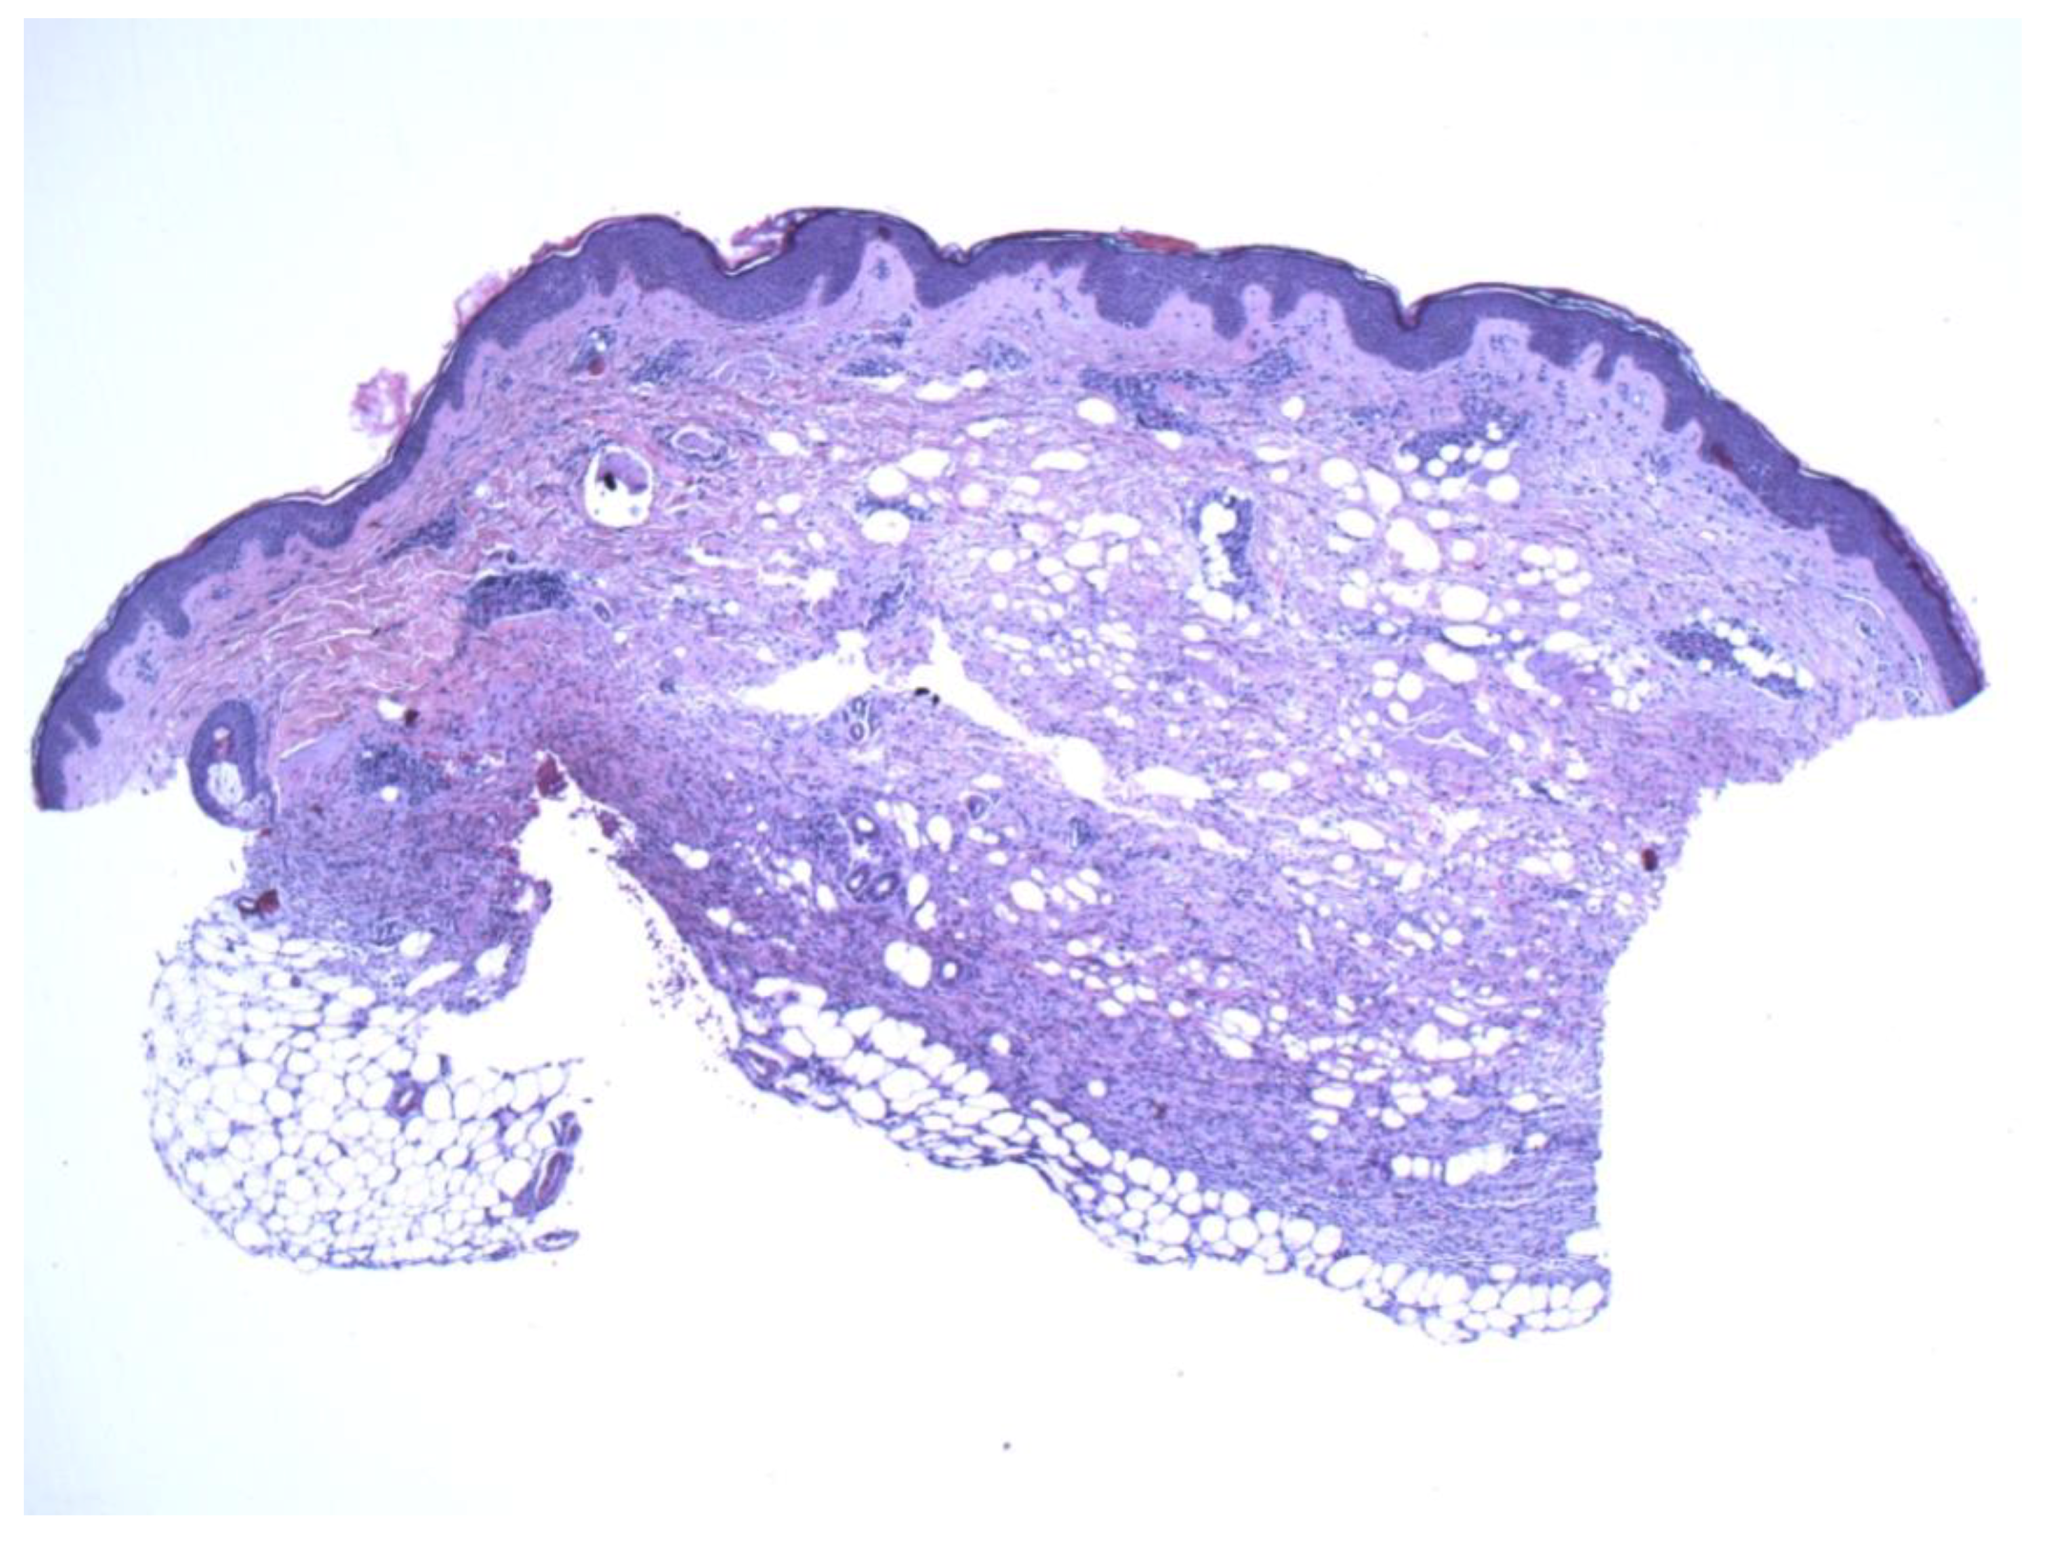

Figure 2.

A thin strip of spindle cells is noted in the deeper dermis with subjacent fat. The mid and superficial dermis show sparse spindle cells with atrophic changes (4×).